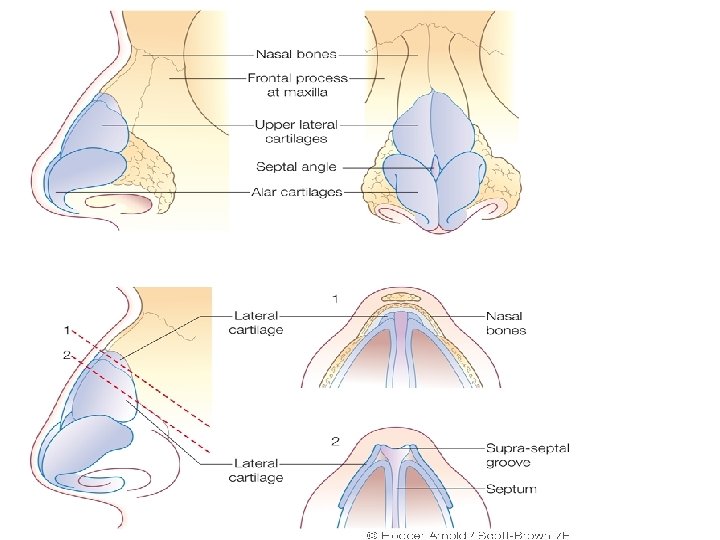

EXTERNAL NOSE • External nose is shaped like a pyramid with its root up and base directed downwards. • Consists of osteocartilagenous framework covered by muscle and skin.

• • Osteocartilagenous framework: Upper 1/3 rd - bony Lower 2/3 rd – cartilagenous Bony framework a) Nasal bones b) Nasal processes of frontal bone c) Frontal processes of maxilla

• • • Cartilagenous framework a) Upper lateral cartilages b) Lower lateral cartilages (alar cartilages) c) Lesser cartilages (sesamoid cartilages) d) Septal cartilage